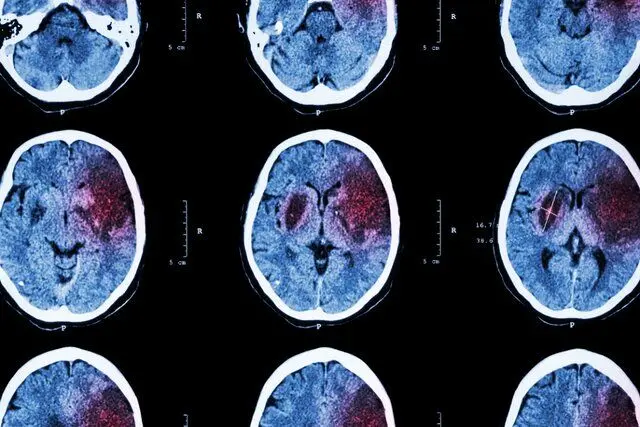

سکتههای مغزی و قلبی این روزها به واکسنهای کرونا ربط دارد؟

این روزها نگرانیهایی در ارتباط با بعضی بیماریها و سکتههای مغزی و قلبی به ویژه در افراد میانسال وجود دارد که با توجه…